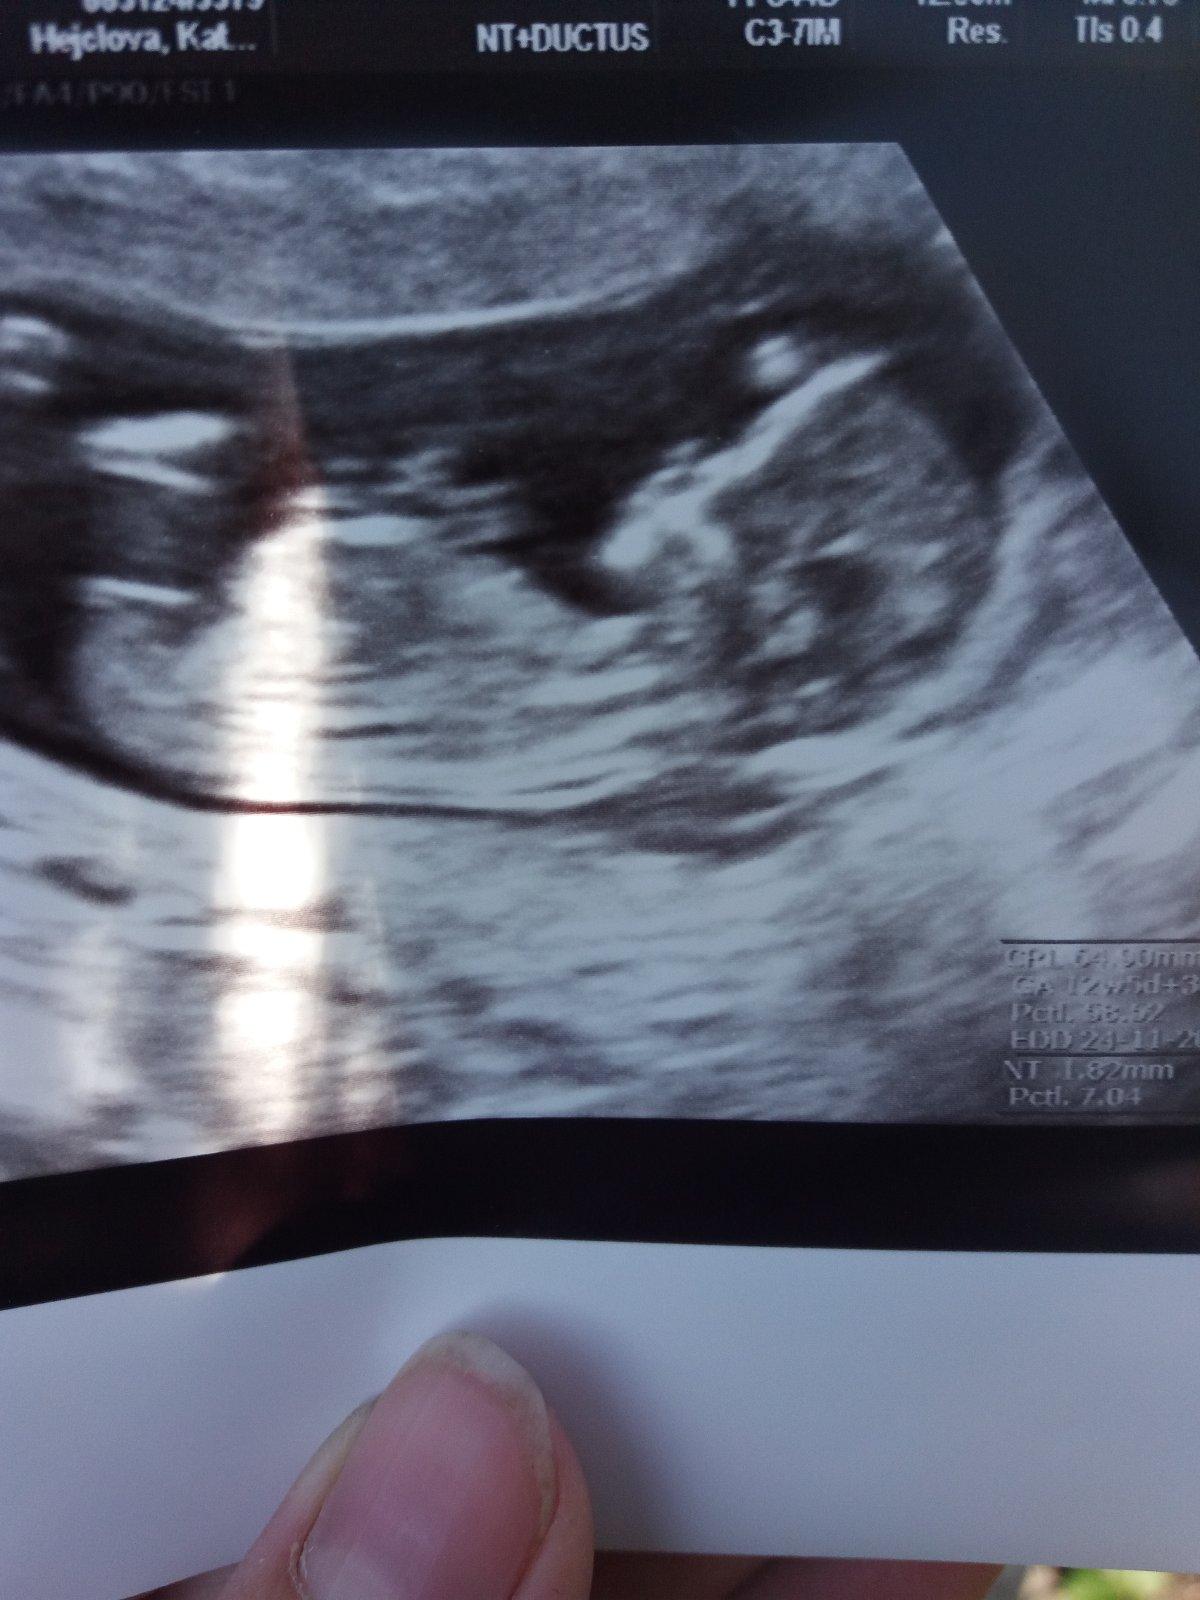

Je to holčička nebo chlapeček? Foto ultrazvuku

Nejsem si úplně jistá, jestli je pohlaví na té fotce vidět právě. Ale je to chlapeček 🙂